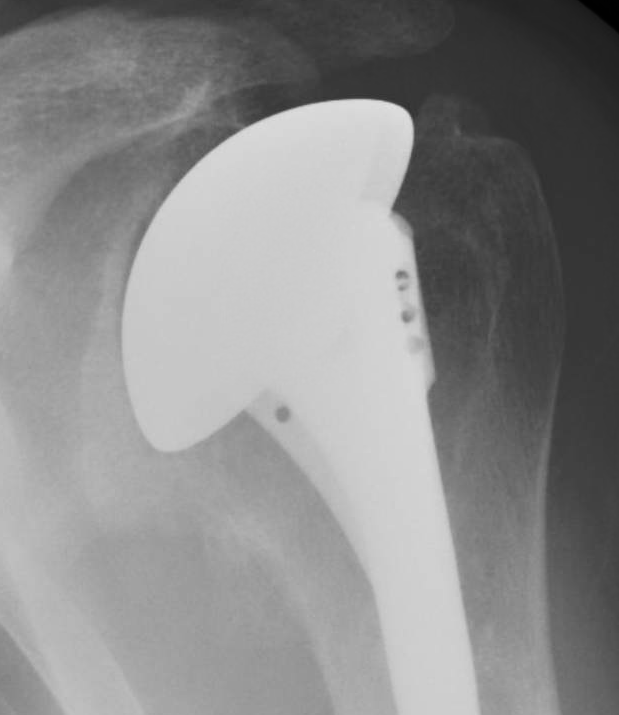

Different Types of Rotator Cuff Surgery Rotator Cuff Surgery Gone Bad rotator cuff tears may be repaired with surgery. rotator cuff tears are a common cause of shoulder pain, stiffness, weakness, and loss of motion and function. Until then, recovery entails pain control, rest, and physical therapy to regain shoulder strength and range of motion. failure of rotator cuff repair surgery to achieve a durable reattachment of the. Rotator Cuff Surgery Gone Bad.